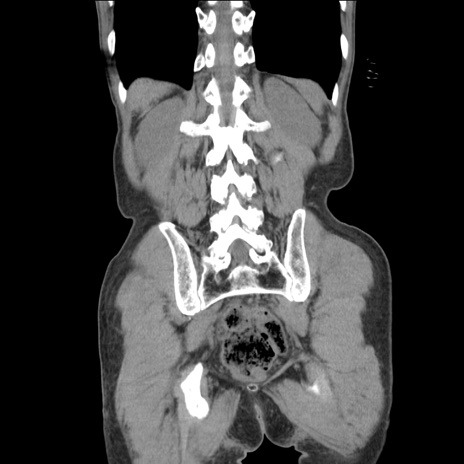

横断像

【症例】 60歳代男性

【主訴】 下腹部痛

【現病歴】 本日夜中より下腹部痛の症状認め、受診。

【既往歴】 膀胱癌(膀胱全摘+尿管皮膚瘻術) 、胃癌術後

【身体所見】 BT 35.3℃、PR 58/min、BP 136/98mHg、腹部平坦、軟、腸蠕動音±、ストマ留置あり、左上腹部~正中部に圧痛あり、反跳痛なし。

【データ】WBC 5100、CRP0.01